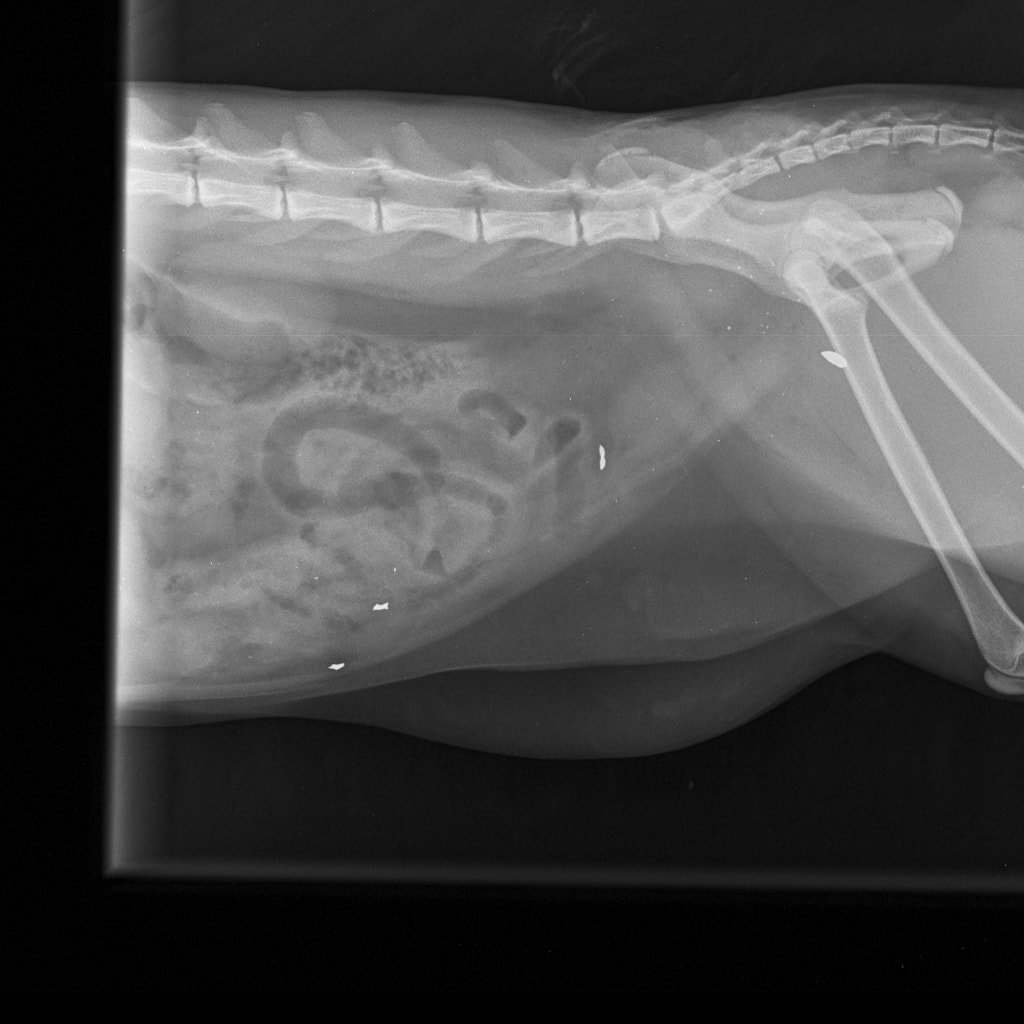

– Nikako ne mogu razumjeti da mi je netko namjerno ubio životinju. I to metkom koji se rasprsnuo u tijelu malene životinje što nije metak iz zračne puške. To se lijepo i vidi na rendgenskoj snimci koju smo obavili u Veterinarskoj ambulanti Majcan. U svakom slučaju, prijavili smo sve policiji koja će, iskreno se nadam, čim prije pronaći krivca – rekla nam je tužna vlasnica ubijene životinje.